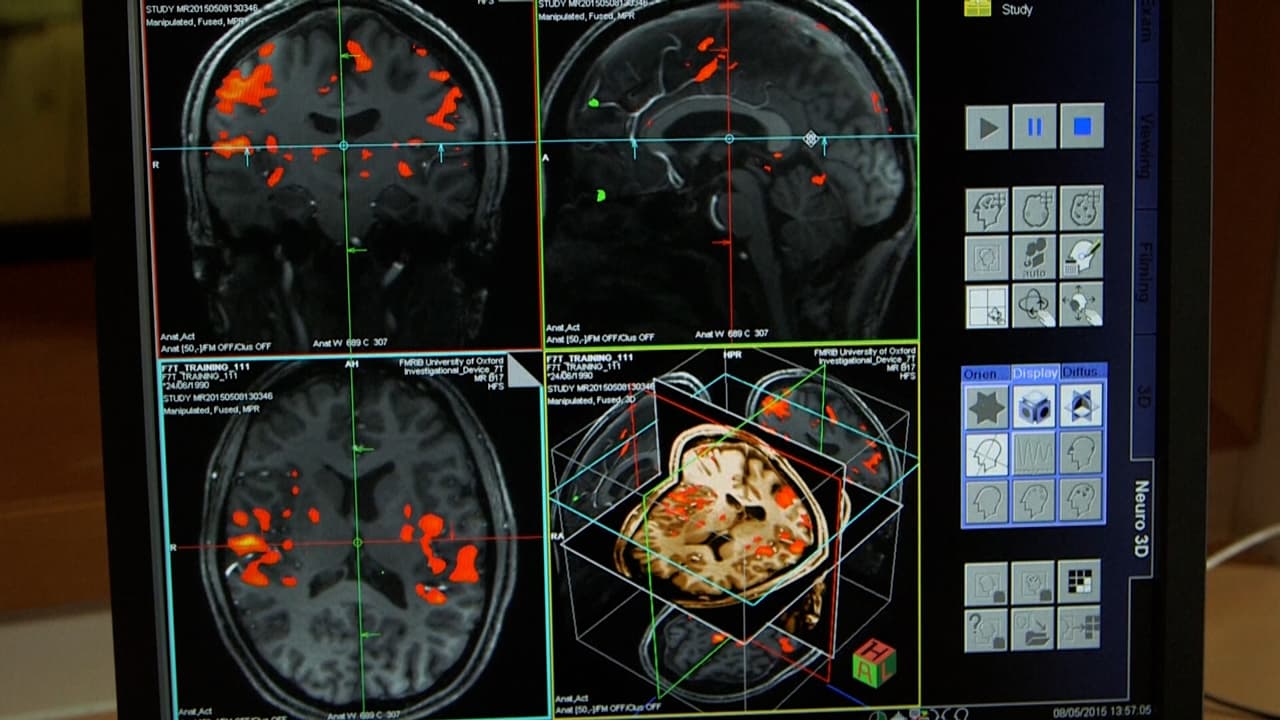

El estudio utiliza un robot para colocar quirúrgicamente un implante de interfaz cerebro-ordenador en una región del cerebro que controla la intención de moverse.